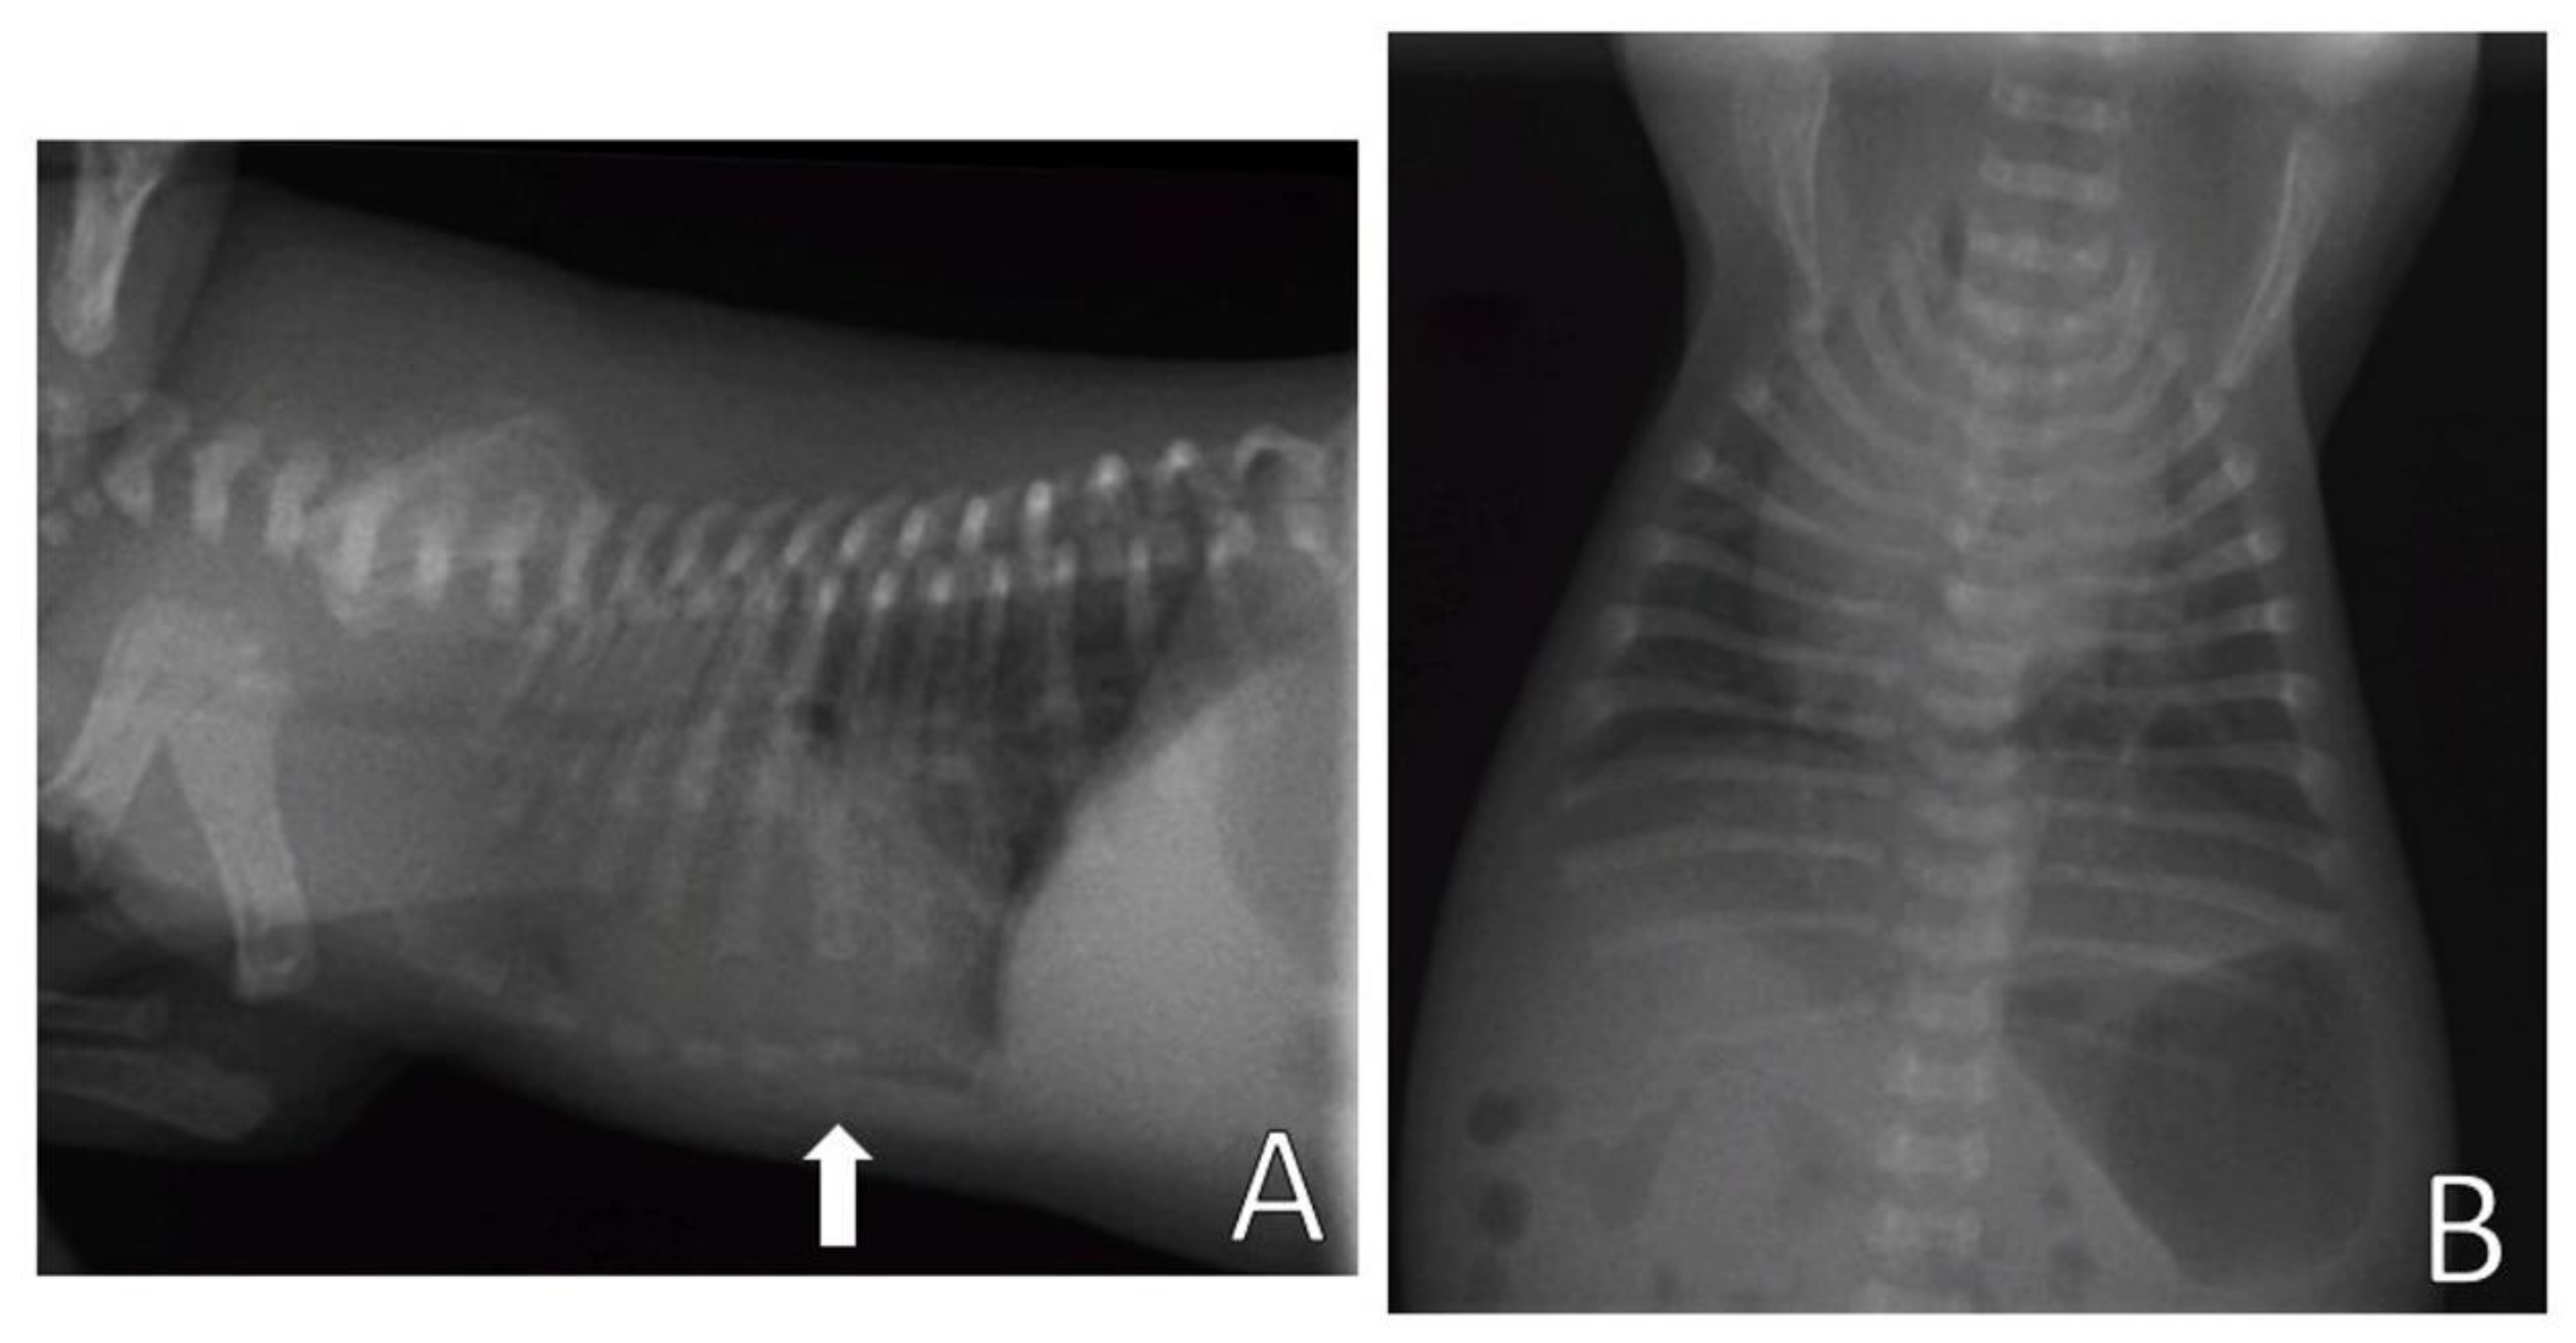

On the return, eight days after the beginning of management, chest remodeling was observed, with the thorax correctly aligned, with absence of depression in the sternum bone region (Figure 8) and absence of respiratory distress. Video S2 demonstrates the respiratory pattern without alterations, with absence of substernal retraction during inspiration.

Figure 8.

(A) Patient before splint management, presenting chest depression in the sternum bone region (arrow). (B) Patient after splint removal presenting chest with the absence of ventrodorsal narrowing in the sternal region (arrow) after noninvasive treatment.

On the return, six days after the beginning of management, the neonate presented a chest wall without alterations, observing the remodeling of the thorax, absence of depression in the sternum region (Figure 13), regular respiratory pattern, absence of substernal retraction during inspiration (Video S4) and pink mucous membranes.

Figure 13.

Patient after splint removal. Thorax presenting absence of ventrodorsal narrowing in the sternal region (arrow) after noninvasive treatment.